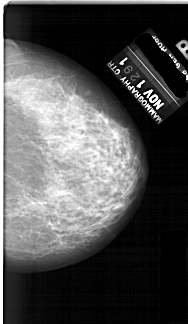

A_1691_1.RIGHT_MLO

RIGHT_MLO LINES 6586 PIXELS_PER_LINE 3721 BITS_PER_PIXEL 12 RESOLUTION 43.5 NON_OVERLAY